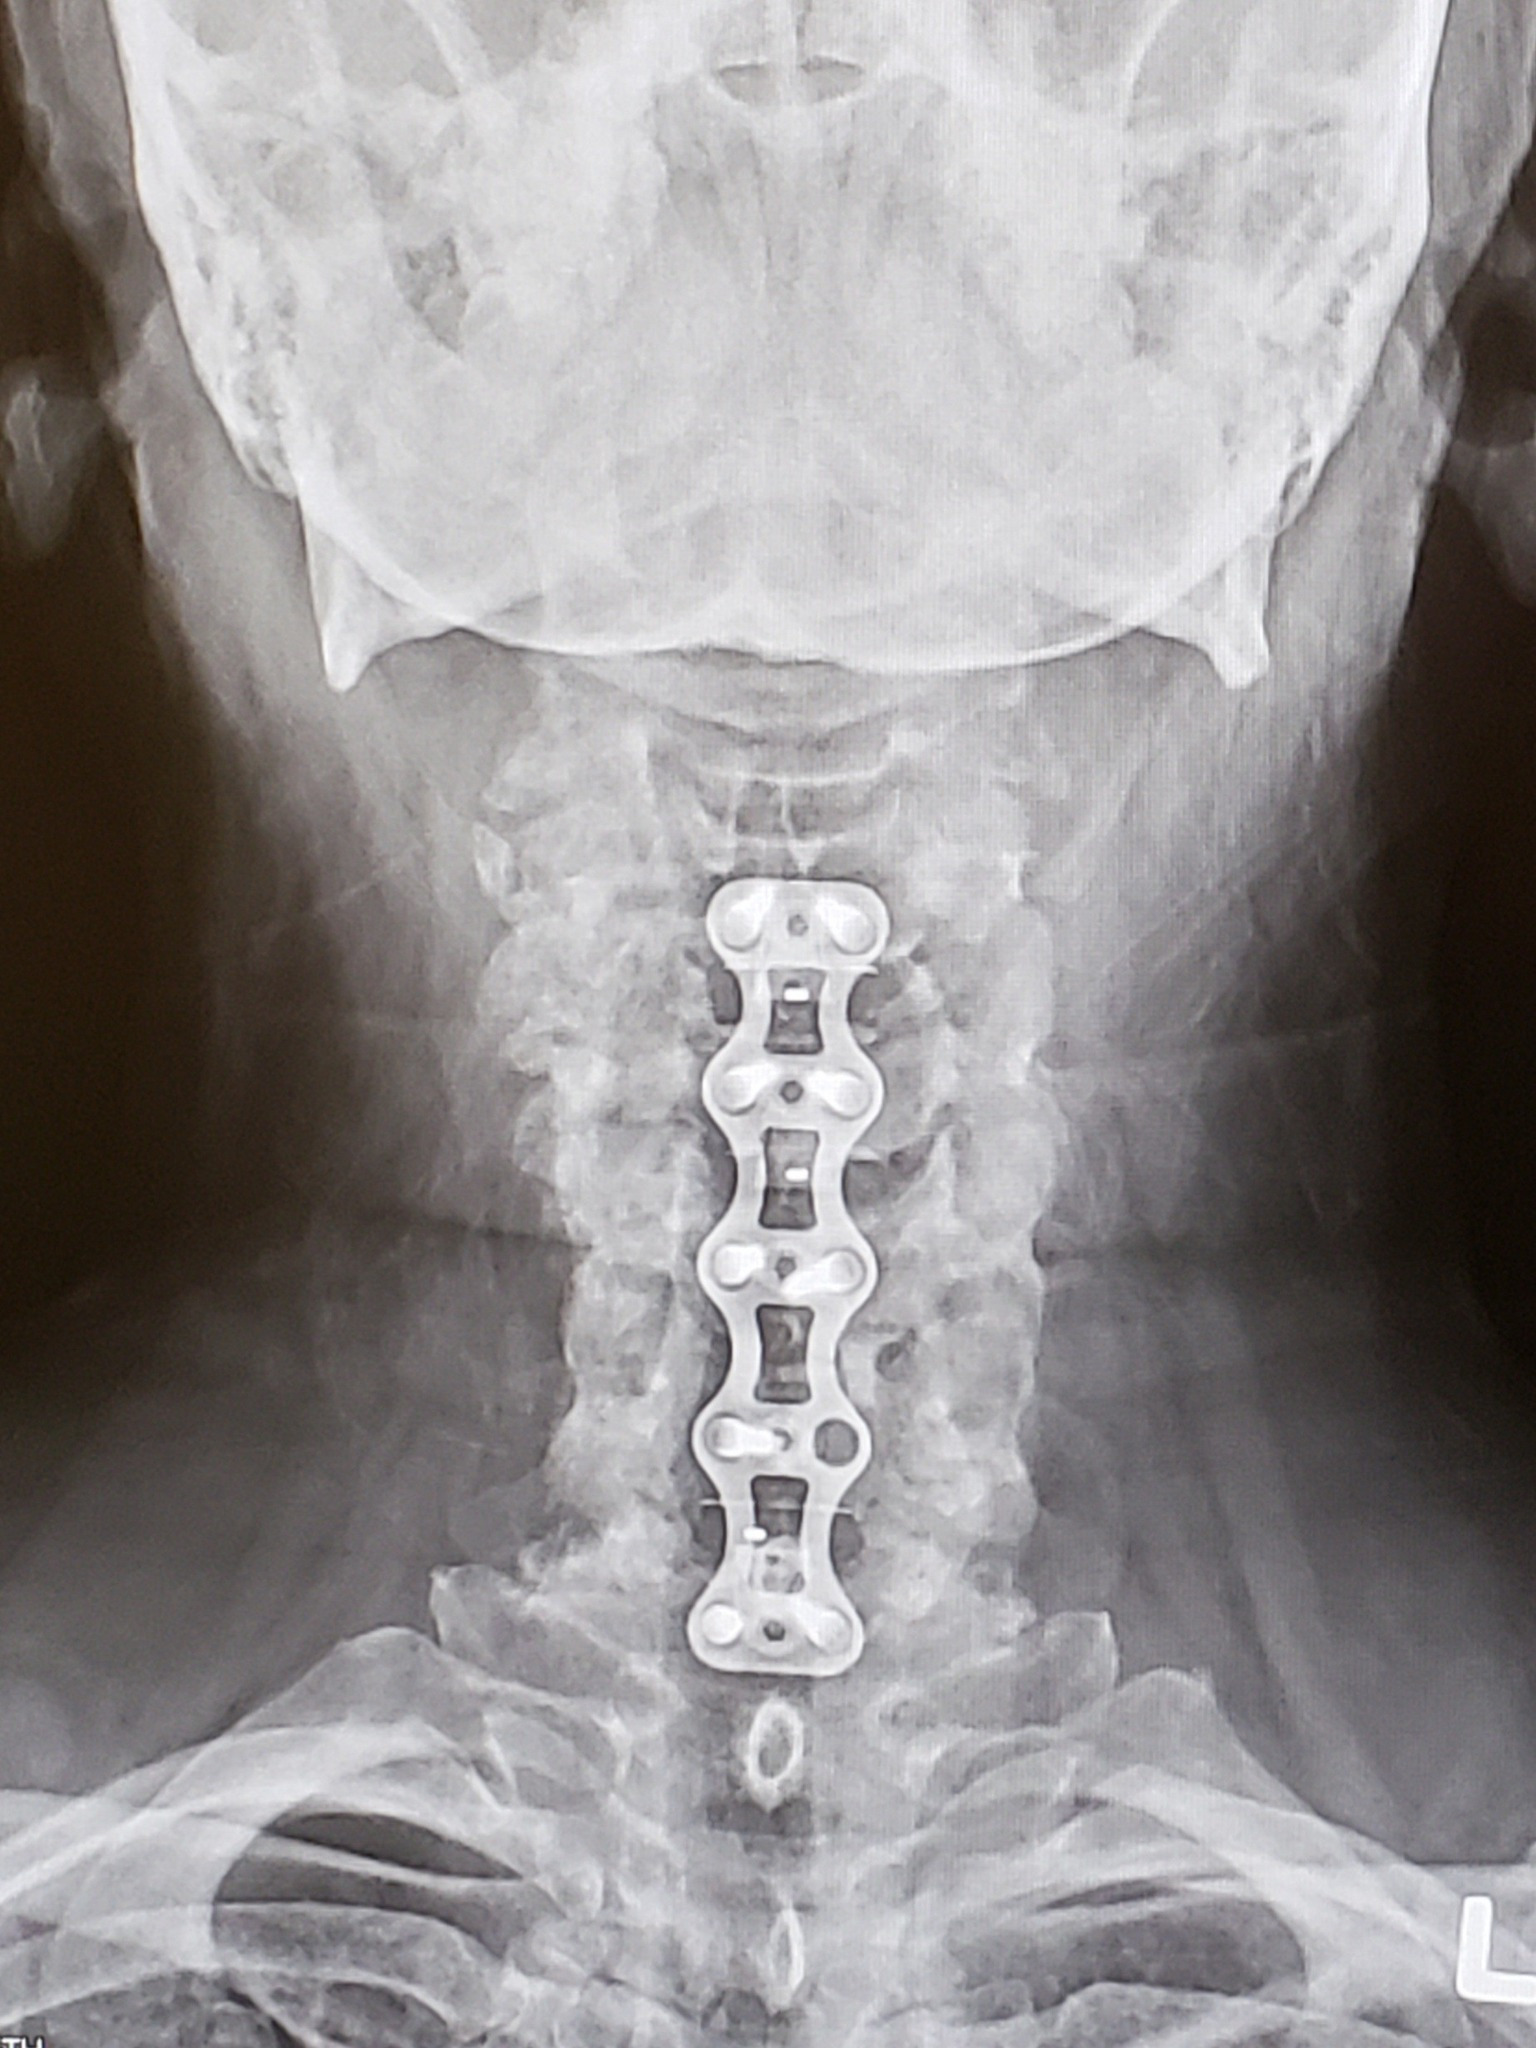

Hello, my name is Tamyra Carter. Unfortunately, I have lost finances due to recovering from a lower leg fracture and extensive neck surgery. I've been scared and embarrassed to write this, but I had a friend encourage me to do so. I am unable to work yet until neck heals. So, that is taking a toll as well. If possible, please consider giving to help w/ rent, utilities, food, etc. Thank you so much!

-ski accident, first neck surgery and off work for over a year.